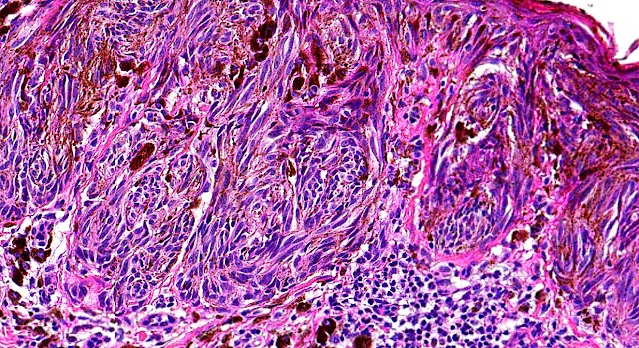

Dermatopathology Case 185

A 10-year-old boy, presented with an uniformly pigmented

lesion with regular margins. The lesion was located on the

medial aspect of the left knee.

Surgical excision with a 2-mm margin was performed.